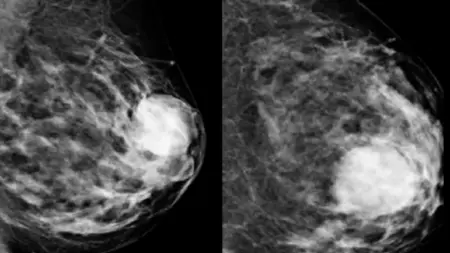

Πολλά από αυτά τα σημάδια μπορεί να οφείλονται και σε καλοήθεις (μη καρκινικές) παθήσεις του μαστού. Τα συμπτώματα αυτών των καταστάσεων μπορεί να περιλαμβάνουν ογκίδια, πόνο ή έκκριση από τις θηλές. Κάποιες καλοήθεις καταστάσεις μπορεί να φανούν σε μαστογραφία.

Αν παρατηρήσετε κάποιο ογκίδιο ή άλλη αλλαγή στον μαστό σας, κλείστε ραντεβού με γιατρό ή άλλο επαγγελματία υγείας. Αναφέρετε οποιεσδήποτε αλλαγές στους μαστούς σας, ακόμα κι αν μια πρόσφατη μαστογραφία έδειξε ότι δεν υπάρχει καρκίνος.

Ο καρκίνος του μαστού παραμένει μια από τις σημαντικότερες προκλήσεις υγείας που αντιμετωπίζουν εκατομμύρια άνθρωποι παγκοσμίως, κυρίως γυναίκες. Ωστόσο, οι ιατρικές εξελίξεις, η αυξημένη ενημέρωση και η έγκαιρη διάγνωση έχουν βελτιώσει σημαντικά τα ποσοστά επιβίωσης και την ποιότητα ζωής πολλών ανθρώπων. Η κατανόηση του καρκίνου του μαστού — των συμπτωμάτων, των αιτιών και των σταδίων του — είναι καθοριστική για να αποκτήσουμε τον έλεγχο της υγείας μας. Οι τακτικοί αυτοεξετάσεις, οι προληπτικές μαστογραφίες και οι ιατρικοί έλεγχοι αποτελούν τη βάση της έγκαιρης διάγνωσης. Η αναγνώριση του καρκίνου σε πρώιμο στάδιο σημαίνει συχνά απλούστερη θεραπεία και καλύτερη πρόγνωση.